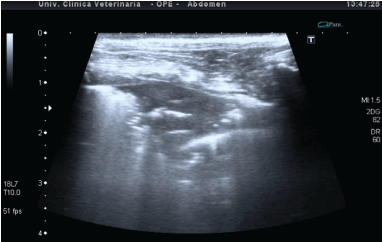

在我们的研究中,并证明是一种高效,安全,可行的方法。高诊断准确性促进了急性消化患者肺部肺病的诊断。最后,胸部美国很容易重复,让患者在重症监护室内每天密切监测几次。实时超声图像快速发展,超声波可用于监测患者随访期间的治疗响应。用基因型肺水肿纳入本研究的患者用利尿疗法治疗,并在几个小时后经历了第二次超声检查。表现出B线的减少。抗凝血剂和肺挫伤中毒病例中的超声检查显示出在逆后几天的时间进化,随着与空气支气管图相关的肺结核的变化(图5)。

图5:抗凝血剂中毒在狗身上;(左)一天,注意汇合B线的存在,提供白色肺部。(右)第二天,用肺结核和空气支气管的图像修改。